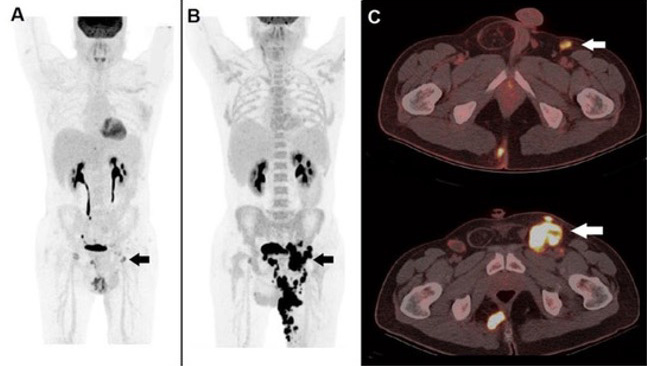

Targets PSMA to detect prostate cancer at staging and recurrence, delivering high‑contrast pelvic imaging.